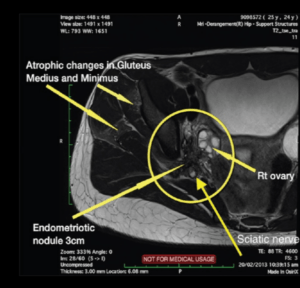

O ultrassom com preparo intestinal e a ressonância magnética são os melhores exames para o diagnóstico da endometriose profunda, devendo ser realizados por um especialista em endometriose.

Para a endometriose no nervo ciático o exame de escolha é a ressonância magnética.

Imagem de um artigo científico encontrado em: Saar TD, Pacquée S, Conrad DH, et al. Endometriosis Involving the Sciatic Nerve: A Case Report of Isolated Endometriosis of the Sciatic Nerve and Review of the Literature. Gynecol Minim Invasive Ther. 2018;7(2):81-85. doi:10.4103/GMIT.GMIT_24_18